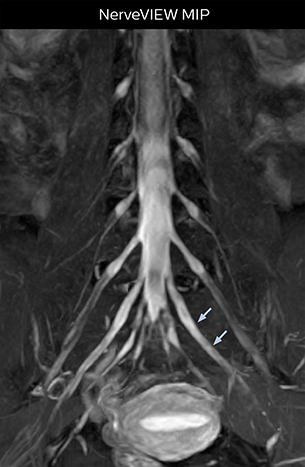

Northern Fukushima Medical Center (NFMC) Imaging Center uses the 3D NerveVIEW sequence for performing MR neurography, particularly in patients with pain and weakness in the lower limb. “It is included in about 20% of the approximately 150 lumbar spine MRI exams each month at NFMC, and can help us to determine if structures are impinging on the nerves,” says Hajime Tanji, RT, MRI technologist at NFMC.

“NerveVIEW is really useful for those cases where a nerve disorder is strongly suspected based on the clinical examination but our regular MRI images do not show any findings. These atypical herniations and spinal canal stenosis, occurring in 5% to 15% of the total lumbar herniation/stenosis cases are our main target when using NerveVIEW,” says Dr. Yabuki.

“Recently, the two surgical methods extreme and oblique lateral interbody fusion (XLIF and OLIF) have become mainstream for minimally invasive treatment of lumbar spinal canal stenosis and intervertebral foramen stenosis. With these surgical techniques, the spine is approached from the flank, and prior knowledge of the exact anatomy of the lumbosacral plexus would be extremely helpful. To that end, high slice resolution (less than 1 mm acquisition) that enables sharper sagittal MPR images will be needed.”

“For both brachial and lumbar plexus, we are currently using a 230 mm FOV and voxels of about 1 x 1 x 2 mm acquired (1 x 1 x 1 mm reconstructed). This provides us a good representation of the nerves, even though this FOV is relatively small. Regarding the inplane resolution, we hope to be able to bring that down to 0.7 mm, similar to our typical 2D multislice T2W images,” says Tanji.

Implementing NerveVIEW without lengthening exam time “The source images of NerveVIEW exhibit a contrast similar to STIR or fat-suppressed T2-weighted images. So, in our neurography exams we are replacing the 2D T2-weighted coronal sequence with 3D NerveVIEW. With this, we add a lot of useful information without adding scan time. This is important for patients with severe lower extremity symptoms, as they often find it difficult to maintain still during the whole MRI examination, so the exam should be as short as possible.” “We have currently implemented 3D NerveVIEW on our Achieva 3.0T dStream MRI system only. Because the 3D NerveVIEW method is based on a background signal suppression technique, we decided to use the high SNR of our 3.0T MRI system for obtaining the best possible visualization of peripheral nerves,” says Tanji. “Where NerveVIEW of the lumbar plexus is currently used as a subroutine scan for patients with strong lower limb symptoms, its use for visualization of the brachial plexus, is currently limited to special cases such as schwannomas and neuritis, usually only 1 or 2 cases per month.”

The addition of the nerve-selective NerveVIEW sequence to its spine MRI protocol has given NFMC competitive advantages, according to Tanji. “Since we started including NerveVIEW routinely, the demand for lumbar spine MRI examinations has increased, especially for pre-surgical planning purposes and for patients with chronic lower extremity symptoms,” he says. “Moreover, because no other hospitals in our region are doing nerve plexus imaging yet, we often receive referrals for MR neurography studies from other hospitals even if they have an MRI scanner. Some requests come from as far as 100 km away. NerveVIEW definitely provides us a competitive advantage.” “Based on our experience, we can certainly recommend NerveVIEW to other centers,” Dr. Yabuki adds. “The sequence opens up many possibilities to facilitate the diagnosis of lower extremity pain and to inform our decision-making regarding therapy and surgery.”